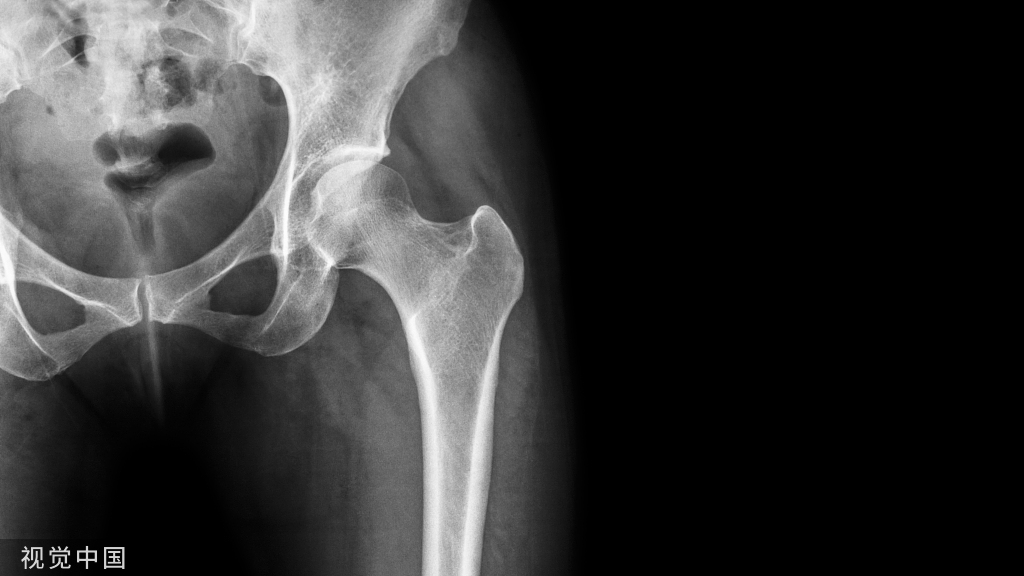

Jones骨折发生在第五跖骨近侧干骺端。该区域是血液供应的分水岭,与骨折的延迟愈合和症状性骨不连的发生率增高有关

血供情况

多支骨骺和干骺端 动脉提供基底部和粗隆部的血运,但只有一根营养动脉从内侧皮质进入骨干的近中 1/3 处为骨干提供血运,此根营养动脉只发出一个纵向的髓内分支供应骨干和粗隆部交界处血运,Jones 骨折很容易造成其损伤,所以此处很容易发生骨延迟愈合或不愈合。

由于跖骨的骨干和干骺端交界处恰好是血供的分水岭,所以急性骨折采用非手术治疗增加了延迟愈合和不愈合的风险。